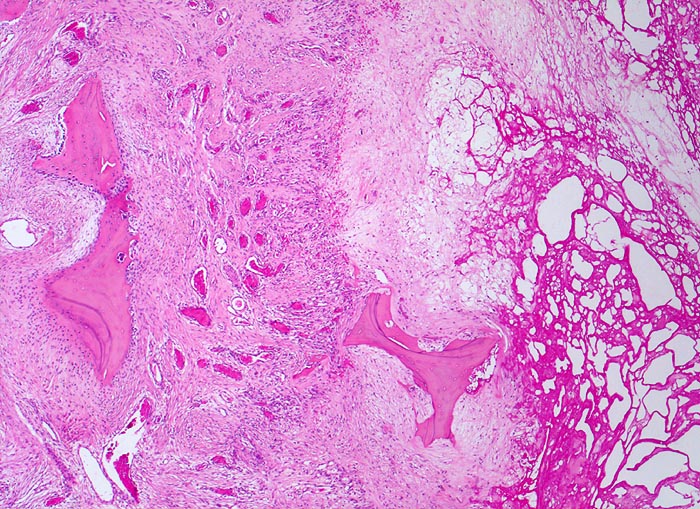

Der progrediente Knorpelverlust führt zum Freiliegen der knöchernen Deckplatte. Der subchondrale Knochen antwortet mit einer elfenbeinartigen Sklerose in Arealen vermehrter Belastung (=Eburnisation). Der traumatisierte subchondrale Knochen kann als Folge einer Knochennekrose pseudozystisch degenerieren (Geröllzystenbildung). Am Rand des Knochens, ausserhalb der Belastungszonen bilden sich irreguläre Knochenneubildungen (Randosteophytenbildung ev. mit Verdoppelung des Gelenkknorpels). Fragmentierungen dieser Osteophyten oder des Gelenkknorpels führen zu intraartikulären freien Körpern (=Gelenkmäuse) und einer Detritussynovialitis (> 1146) (> 1038) (> 539).

• Deformierte Gelenkfläche.

• Weitgehendes Fehlen des hyalinen Gelenkknorpels.

• Sekundäre Sklerose der freiliegenden Spongiosa mit Anbau von breiten Faser- und Lamellenknochensäumen an die alten Bälkchen.

• Herde von metaplastischem Faserknorpel in der Gelenkfläche.

• Randosteophyt, welcher über Resten des dort noch vorhandenen Gelenkknorpels entstanden ist (Verdoppelung des Knorpels).

• Nekrosebezirk in der Spongiosa (Geröllzyste) umgeben von einem Granulationsgewebssaum und Narbengewebe.